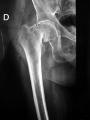

Fractura de caderaLa osteoporosis en el varón es menos conocida que en la mujer, pero su morbi-mortalidad es mayor, según se ha puesto de manifiesto en el Simposio Internacional sobre Actualidad en Osteoporosis, que se está celebrando en la Fundación Ramón Areces, de Madrid.

En el hombre existe una menor pérdida de masa ósea que en la mujer, pero la osteoporosis en el varón presenta una mayor morbi-mortalidad. La mortalidad por fractura de cadera en el hombre con osteoporosis es el doble que en la mujer, según explicó ayer Federico Hawkins, jefe del Servicio de Endocrinología del Hospital Doce de Octubre, de Madrid, que participa en el Simposio Internacional de Actualidad en Osteoporosis, organizado por la Fundación Jiménez Díaz, la Universidad Autónoma de Madrid y la Fundación Ramón Areces, y que comenzó ayer en Madrid.